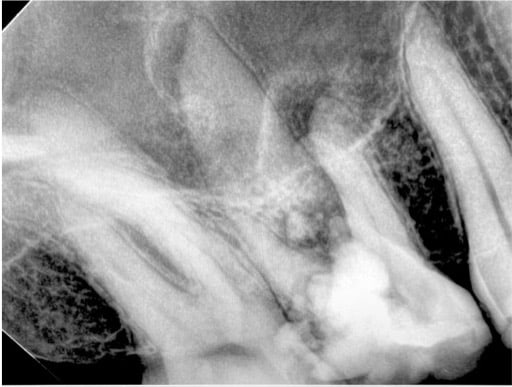

This  maxillary 1st molar extraction (see x-ray) from a few weeks ago with a 35 y.o. woman was tough but it was simply “by the numbers”.

The student I was working with and I took it apart piece-by-piece without removing any buccal bone or a sinus problem.